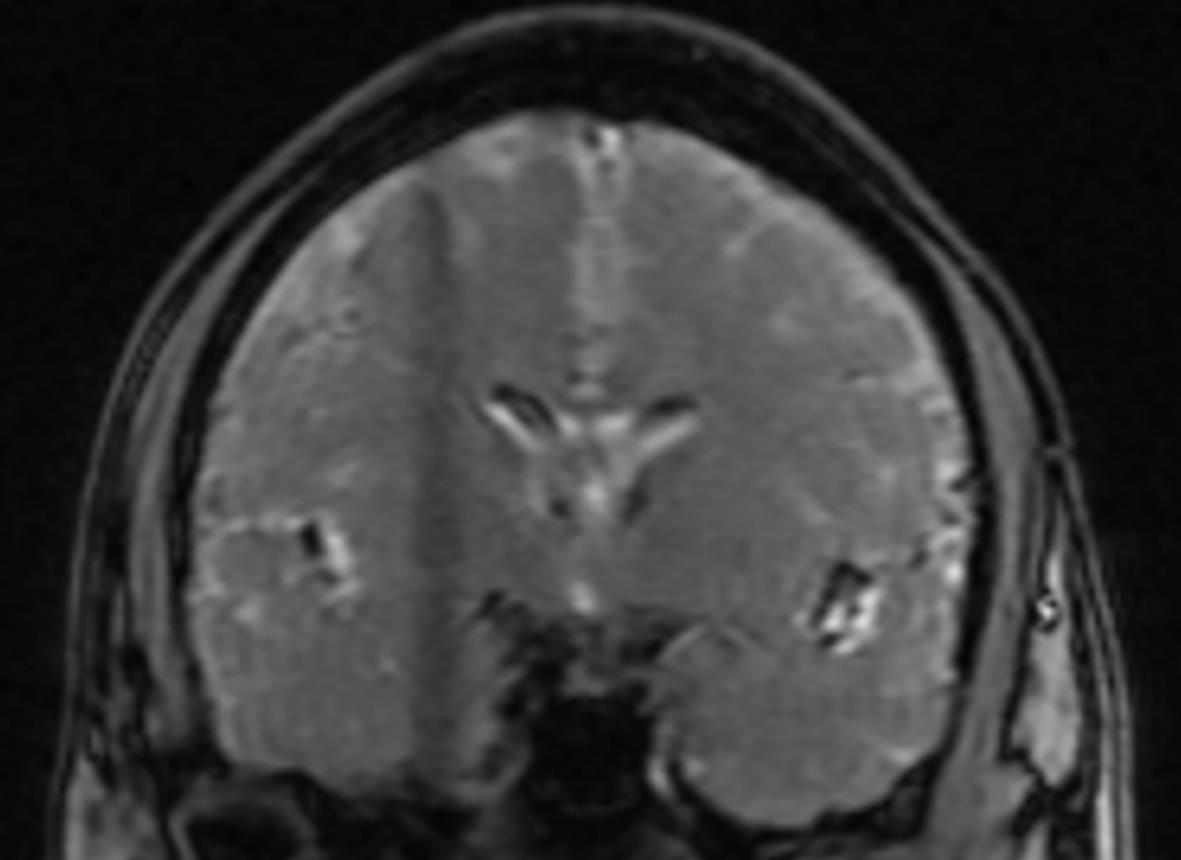

Clinical features of patients with hepatolenticular degeneration aged above 35 years

Hongyun WO, Chengwei KANG, Lei ZHAN, Xiaobing PU

2024, 40(1): 116-120. DOI: 10.12449/JCH240120

Abstract(1368) HTML (933) PDF (819KB)(94)

Abstract:

Objective  To investigate the clinical features of patients with hepatolenticular degeneration (HLD) aged above 35 years.  Methods  A retrospective analysis was performed for the clinical data of the patients with HLD, aged above 35 years, who attended West China School of Public Health, Sichuan University, from April 2018 to April 2023, and according to their clinical symptoms, they were divided into mixed type group with 13 patients, liver type group with 12 patients, and brain type group with 5 patients. Related data were collected, including general information (sex, clinical manifestation, age at confirmed diagnosis, time from initial symptoms to confirmed diagnosis, and family history), laboratory examination (routine blood test, liver and renal function, serum copper, serum ceruloplasmin, urinary copper, and coagulation function), and radiological examination. A one-way analysis of variance was used for comparison of normally distributed continuous data between multiple groups, and the Kruskal-Wallis H test was used for comparison of non-normally distributed continuous data between multiple groups; the Fisher’s exact test was used for comparison of categorical data between groups.  Results  For the 30 patients with HLD, the male/female ratio was 3∶1, and the mean age was 46.13±5.88 years; the patients with positive Kayser-Fleischer ring of the cornea accounted for 43.33%, and the patients with liver cirrhosis accounted for 66.67%. There were significant differences between the three groups in globulin, albumin/globulin ratio, alanine aminotransferase, prothrombin time, international normalized ratio, and activated partial thromboplastin time (F=5.893, 4.513, 4.424, 5.029, 5.248, and 4.942, all P<0.05).  Conclusion  Most patients are male among the patients diagnosed with HLD after 35 years of age, with the main clinical types of mixed type and liver type, and such patients tend to have poor liver and coagulation functions. For unexplained liver function abnormalities and liver cirrhosis in this age group, the indicators such as serum ceruloplasmin and urinary copper should be screened as early as possible, and liver and kidney function and coagulation function should be monitored.